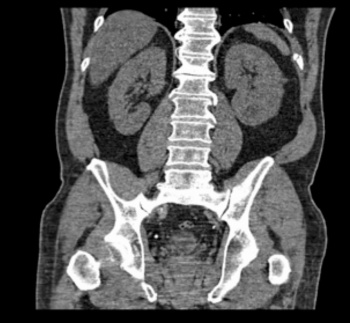

The patient was treated with intravenous fluids, analgesia, nebulisers, antibiotics and steroids and then referred to the medical team with above provisional diagnosis. A CT pulmonary angiography (CTPA) was arranged to exclude above. CTPA showed left 10th rib fracture (see Figure 2), mild atelactic band left lung base and no pulmonary embolism was reported. Renal CT did not show any new stone as cause of left lower rib cage tenderness.

Figure 2. CT image showed left 10th rib fracture, (arrow mark)

Figure 2. CT image showed left 10th rib fracture, (arrow mark)(click to enlarge)